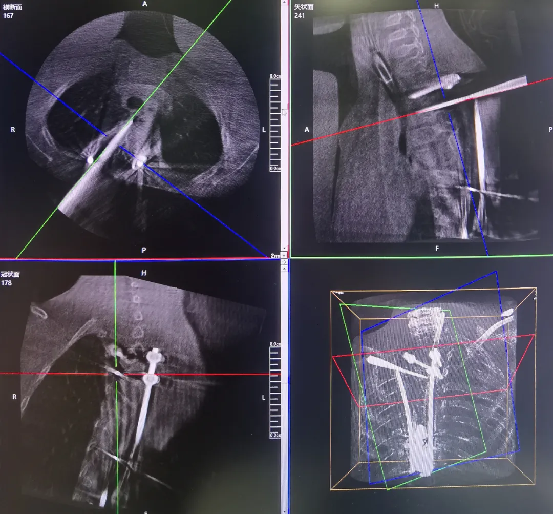

The 3D C-arm performs image acquisition and 3D reconstruction.

Robot-assisted screw insertion path planning

Robot-assisted precise precise screw placement.